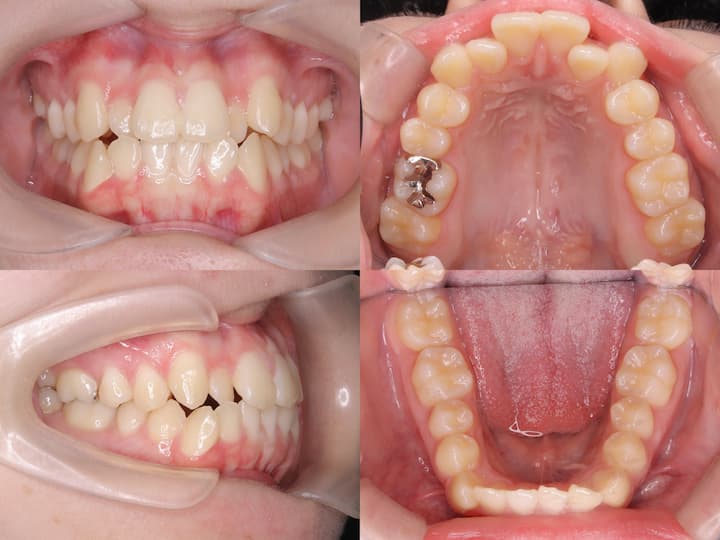

初診時の口腔内所見および頭部X線規格写真分析より、以下の所見が認められました。・上下顎前歯部の叢生

・口唇部の突出感

・AngleⅠ級臼歯関係(良好な臼歯関係)

・下顎骨の後方位(ハイアングル症例)

・下顎下縁平面角の増大

本症例の特徴は、良好なAngleⅠ級臼歯関係を有する一方で、下顎骨の後方位により口唇部の突出感が生じている点です。このような症例では、単純な抜歯スペース閉鎖だけでなく、垂直的な咬合改善が重要となります。

・上下左右第一小臼歯の抜歯による叢生の改善